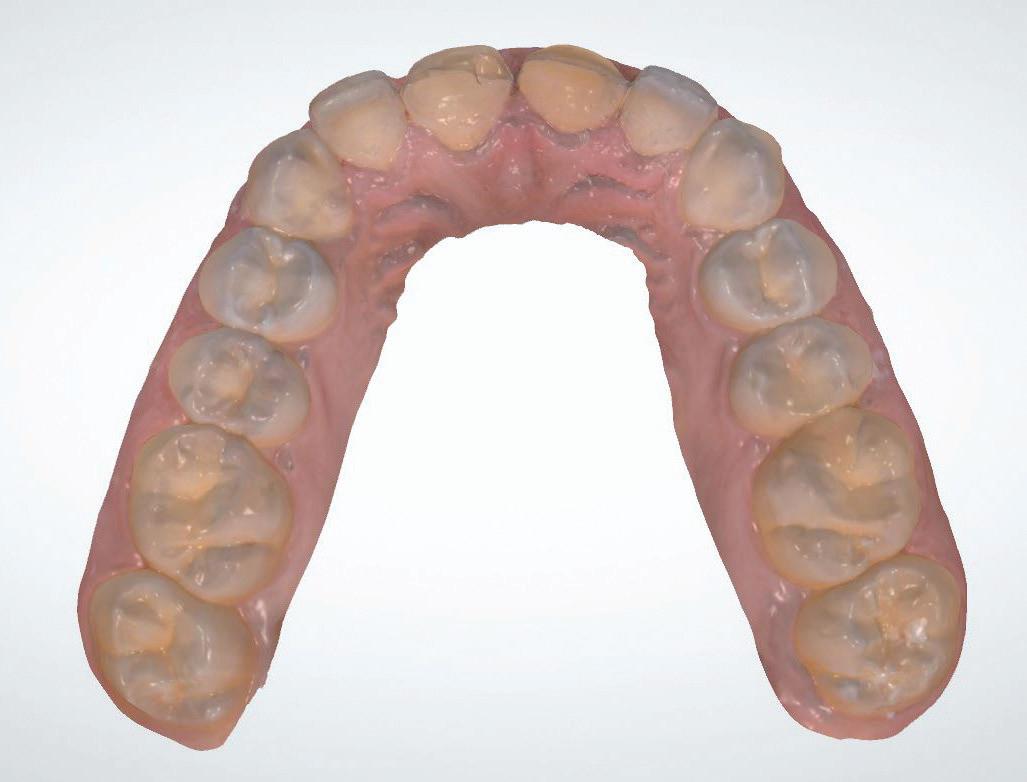

protection from needle stick injuries

security

for the patient

Transparent